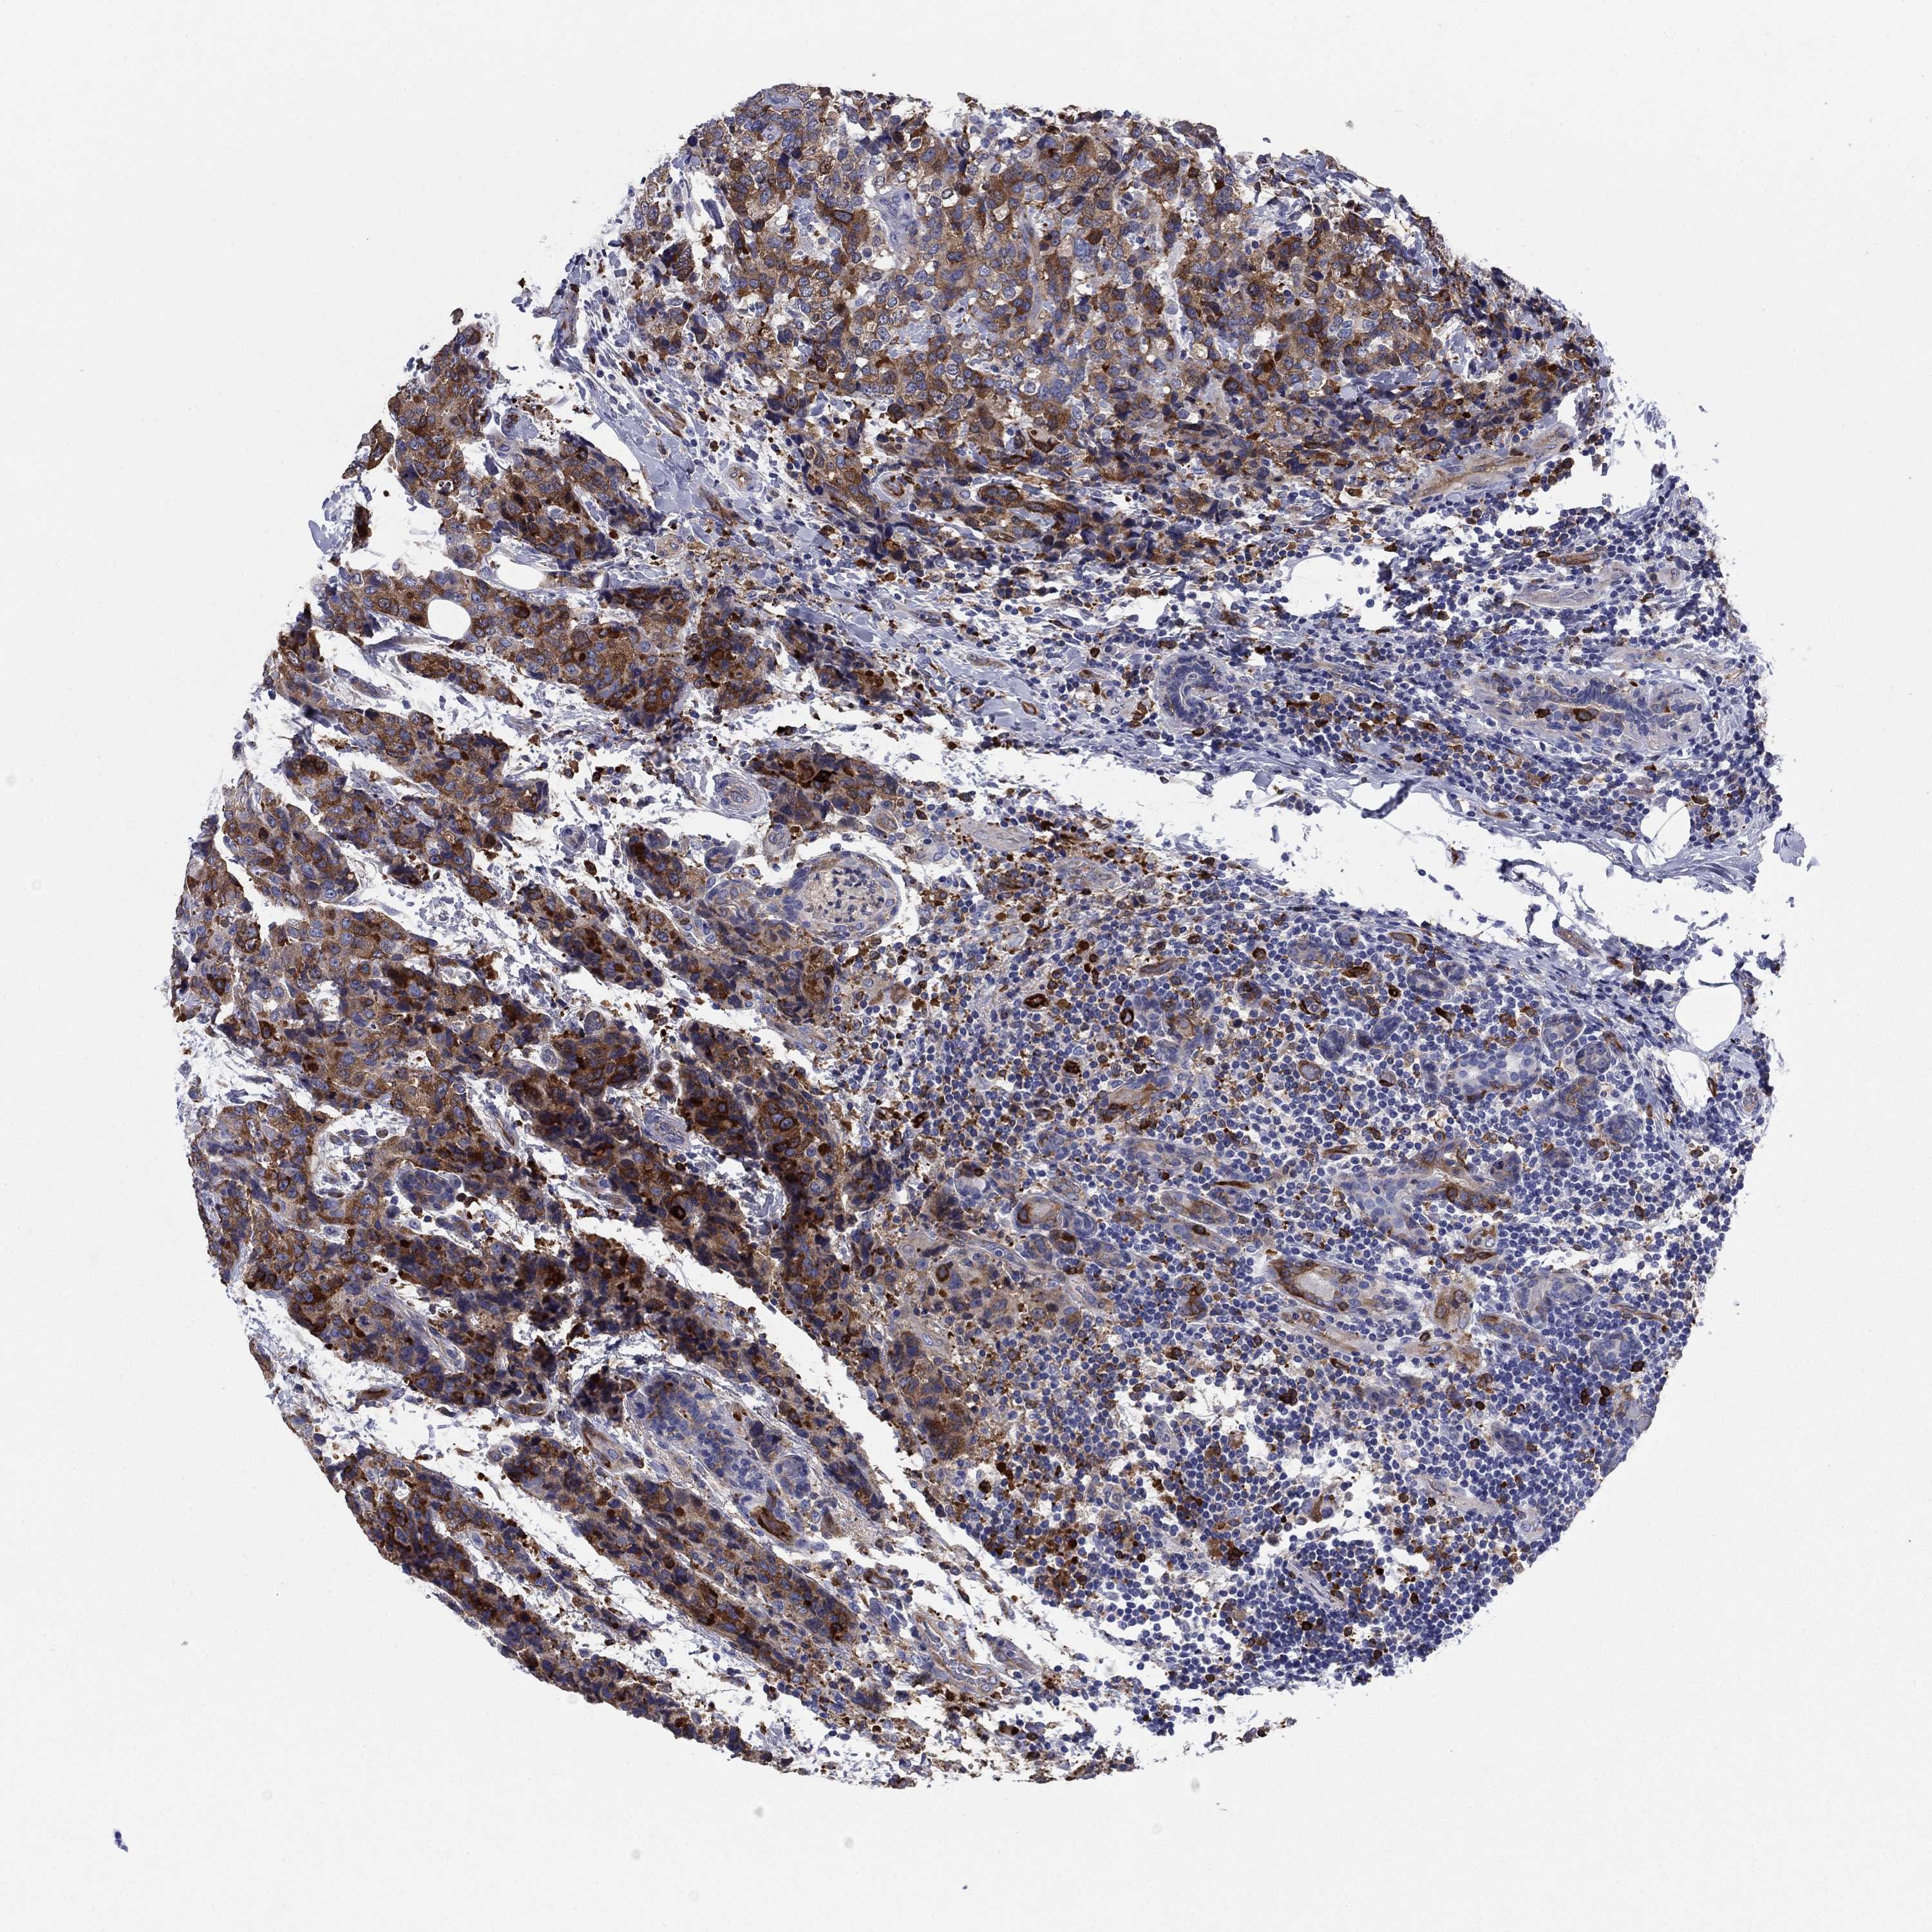

CANCER BREAST CANCER Show tissue menu

BRCA TCGA BRCA VALIDATION PROTEIN EXPRESSION